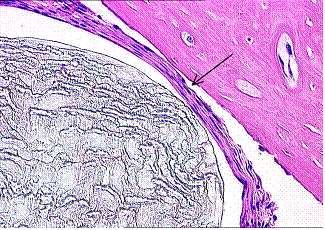

Следует отметить, что на начальных этапах и до 30 суток различия в группах наблюдения по характеристикам периимплантатных тканей были незначительными, в этой зоне преобладали реактивные изменения на экспериментальное воздействие (пропил кости), сопровождавшиеся резорбтивными реакциями кости, воспалением, и образованием клеточноволокнистой соединительной ткани, отделяющей имплантат от костной ткани (рис. 1, 2). Лишь с увеличением сроков наблюдений до 90 суток отмечалось нарастание признаков остеоинтеграции в группах МБНП, однако наиболее чётко этот тип реакции определялся в образцах с покрытием Ti-Ca-P-C-O-N.

Рис.1. Имплантат с покрытием Ti-Ca-P-С-O-N, 30 суток. Плотное спаяние кости с имплантатом на значительном протяжении. Х100. |

Рис.2. Титановый имплантат без покрытия, 30 суток. Имплантат частично вмурован в кость. В области соединения видны волокнистые структуры. Х100. |